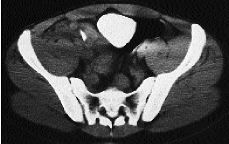

Luxación dorsal del trapezoide

Dorsal dislocation of the trapezoid